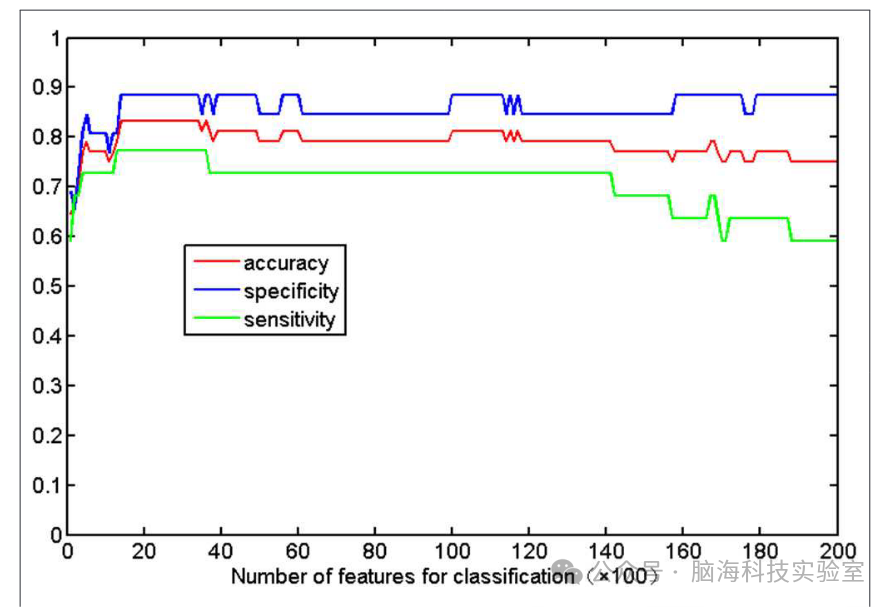

图2展示了基于不同数量的FA特征的准确率、敏感性和特异性的详细结果。当特征集的规模较小时,输入数据无法提供足够的信息来训练出一个可靠的模型;而如果特征集规模过大,输入数据中会出现冗余或不相关的信息,从而导致机器学习的性能下降。只有当选择了适当的数据集时,分类算法才能达到最佳性能。当选择特定数量(1,400到3,400之间)的特征时,可以获得最佳的分类准确率。因此,研究选择了排名前2,400(1,400和3,400之间的中间值)的特征作为最优特征。利用这些具有区分能力的特征,研究确定SVM分类器的准确率可以高达83.33%(敏感性=77.27%,特异性=88.46%,P=0.0001)。以泛化准确率作为统计变量,估计的置换分布如图3所示,表明分类准确率大于83.33%的概率非常低(P=0.0001),这表明研究的结果高度可靠。

图2